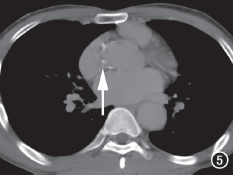

MDCT动脉造影:左主干、前降支近中段、回旋支、右冠状动脉开口部及第二转折处管壁弥漫软斑块,多发中到重度狭窄改变;主动脉及头臂动脉管壁广泛不规则增厚,管腔不规则,主动脉全程管径增宽,以降主动脉下段、腹主动脉为著,内可见附壁血栓形成(图5、6)。

图5 主动脉瓣上管壁钙化(箭)。